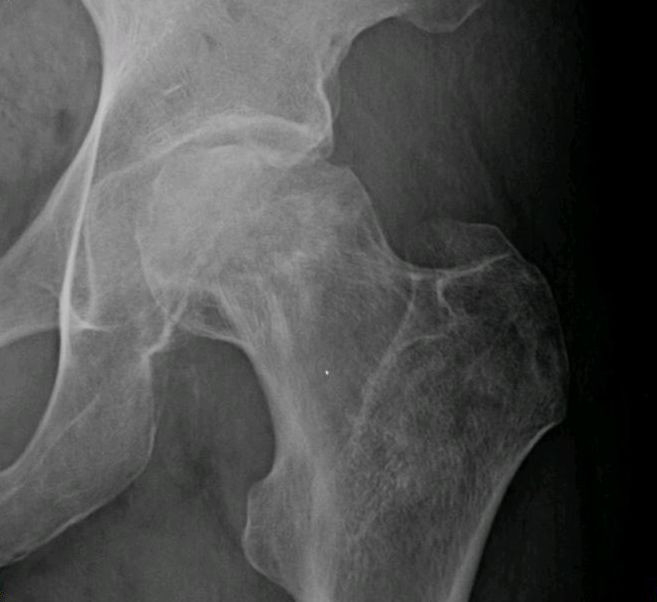

Scientists have also shown that the bisphosphonates bind to bone tissues, but there are many reports of unusual, low-impact bone fractures of the thigh in patients who are taking bisphosphonates such as alendronate / Fosamax for several years as a treatment for osteoporosis or for osteopenia. These unusual fractures often occur after the patient experiences pain in the affected thigh before the fracture occurs and despite having a normal appearance on x-ray, these patients often experience a significant delay in bone healing. So, while bisphosphonates may seem to increase bone density in patients, some scientists have speculated that oversuppression of bone tissue turnover actually causes the bones to become brittle and prone to fracture.

So while your doctor may recommend bisphosphonates to increase the density or strength of your bone tissues, the fact remains that bisphosphonates do not prevent the bones from breaking. In fact, bisphosphonates increase the likelihood of bone fractures and they increase the time it takes for bone fractures to heal. This makes sense because the presence of a carbon atom in these pyrophosphate analogs would disrupt the natural phosphate-calcium crystalline shape that is necessary for strong bones and teeth.

Though bisphosphonates are often prescribed to increase bone density, they don't reduce bone fractures and in fact, bisphosphonate exposure is associated with a certain type of bone fracture in the femur and the death of bone tissues in the jaw.